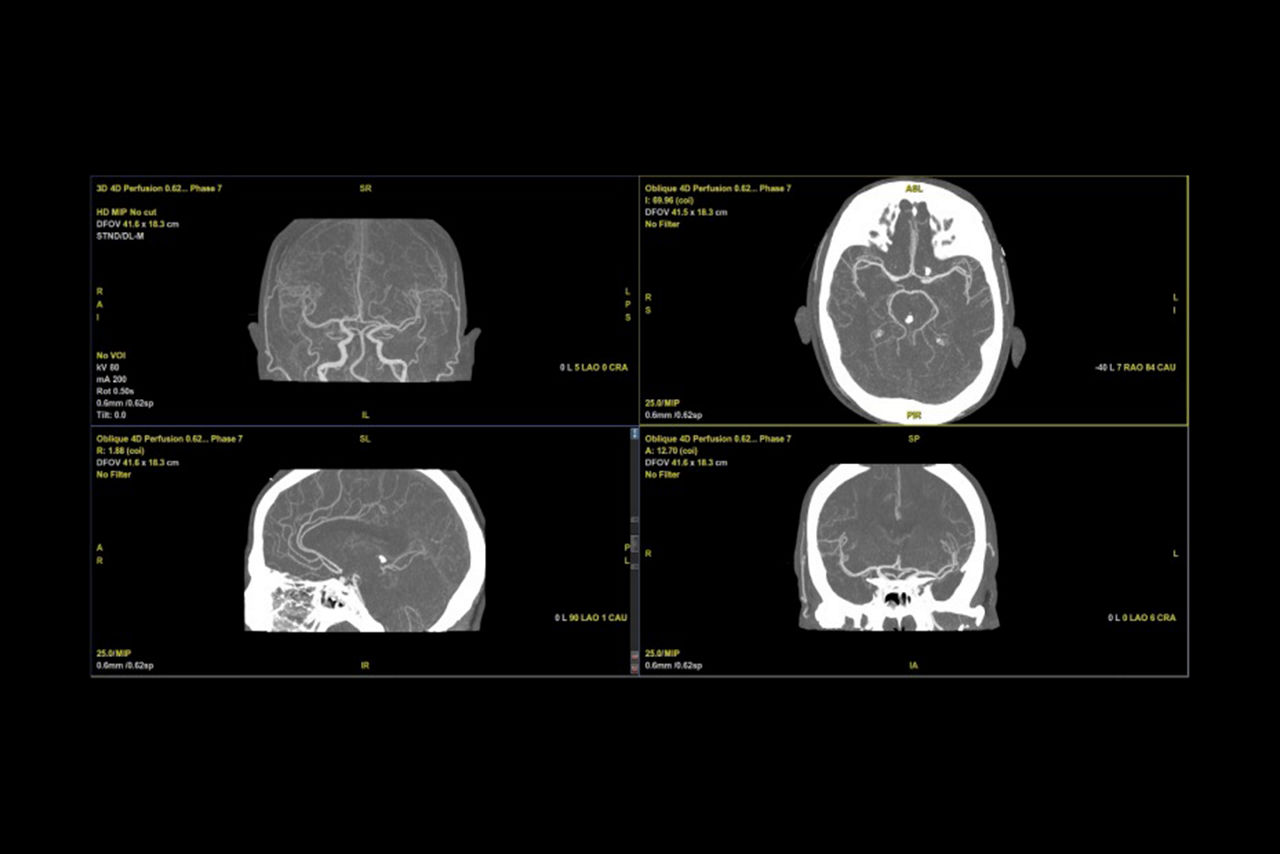

Bone-free dynamic visualization of vascular anatomy.

Allows vascular diagnoses using dynamic CT angiography.

Extracts data from scan and visualizes the flow of contrast from the arteries to the veins.

• 4D Neuro Digital Subtraction angiography (DSA) automatically performs image registration, then removes bone.